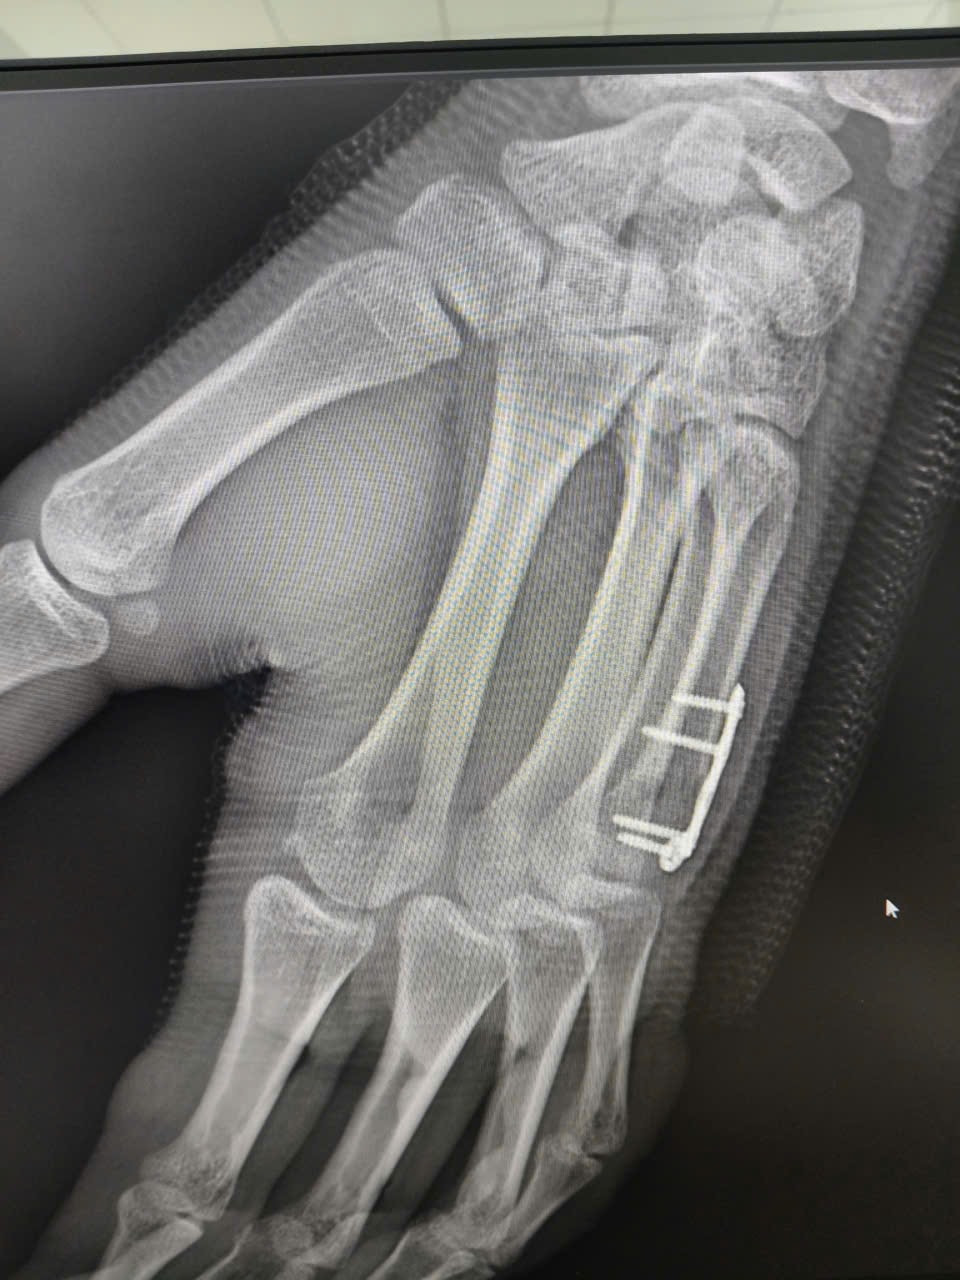

Cú đấm 'định mệnh' khiến nam sinh gãy xương bàn tay sau trận boxing

(CLO) Một nam sinh 17 tuổi vừa phải nhập viện phẫu thuật sau khi bị gãy cổ xương bàn tay số V do chơi boxing nhưng chủ quan không đi khám suốt nửa tháng.